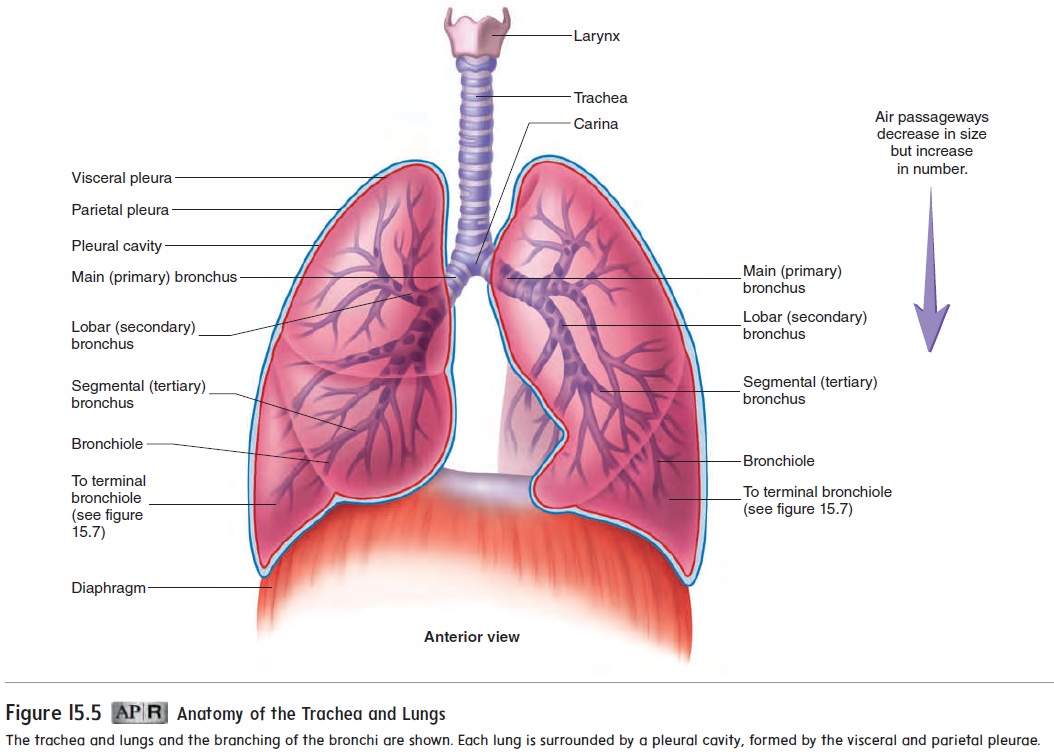

anatomy lungs respiratory system physiology human nurseslabs lung nursing body right breathing organs left main airways medical its board systems

anatomy surface respiratory physiology examination lung relevant lungs lobe ribs middle lower epomedicine fissure upper posteriorly oblique costal sternum floating

lungs anatomy figure physiology gross labeled major

respiratory anatomy system lung gross apex presentation superior left lungs ppt powerpoint inferior base hilum right fissures pleura slideserve

Lungs lobes fissures right left oblique both teachmeanatomy lung structure thorax fig similar position info. Pin on bronchial anatomy. Topography of the lungs (posterior view) the apex of the lung extends